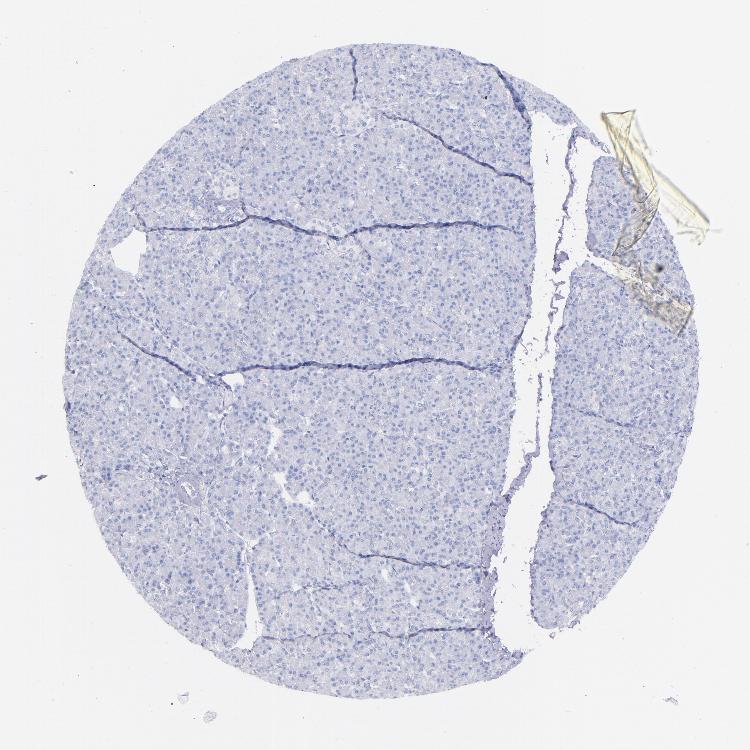

PANCREAS - Antibody stainingi

Antibody staining in the annotated cell types in the current human tissue is reported as not detected, low, medium, or high, based on conventional immunohistochemistry profiling in selected tissues. This score is based on the combination of the staining intensity and fraction of stained cells.

Each image is clickable and will lead to virtual microscopy that enables deeper exploration of all samples and also displays staining intensity scores, fraction scores and subcellular localization as well as patient and tissue information for each sample.

Antibody HPA001616Antibody HPA001645Antibody CAB009809

Exocrine glandular cells Not detectedNot detectedNot detected

Pancreatic endocrine cells Not detectedNot detectedNot detected